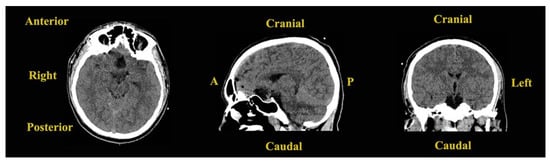

The patient underwent the recommended neuroimaging examination, which showed a suprasellar mass lesion extending into the superior part of the sella and anteriorly over the planum sphenoidale, with a polylobulated aspect, a mixed appearance, and solid, cystic, and hematic components, measuring 25/32/23 mm (transversal/craniocaudal/anteroposterior).

The solid (tisular) component of the mass lesion showed intense gadolinium enhancement without restricted diffusion. Its neighboring structures were represented by the sphenoid sinus (anterior and inferior), the carotid arteries and cavernous sinuses, without invading them (lateral), and a displaced optic chiasm and anterior cerebral arteries (posterior), as well as the optic nerves (lateral). Furthermore, the sella turcica was enlarged, and the hypophyseal gland measured 18/7/12 mm (transversal/craniocaudal/anteroposterior), with a flattened superior contour due to the mass lesion. The paranasal sinus mucosa was thickened, and a right lateral deviation of the nasal septum was observed (Figure 2).

Figure 2. Preoperative contrast-enhanced brain MRI performed before the patient’s admission into our department: (A) axial susceptibility-weighted imaging sequence; (B) axial T2-weighted imaging Fast or Turbo Spin Echo (FSE/TSE) sequence; (C) axial Transverse Relaxation Time (T2)-weighted imaging TSE sequence using dark fluid; (D) coronal T2-weighted dark fluid sequence; (E) coronal T1-weighted dynamic contrast-enhanced sequence; (F) coronal T2-weighted TSE sequence; (G) sagittal T1-weighted TSE sequence; (H) sagittal T1-weighted contrast-enhanced sequence; (I) sagittal T2-weighted TSE sequence.